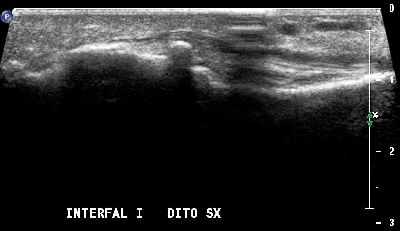

Sesamoide accessorio primo dito interfalangeo (img. 01) Sesamoide accessorio primo dito interfalangeo (img. 01)

Sesamoide accessorio primo dito interfalangeo (img. 02) Sesamoide accessorio primo dito interfalangeo (img. 02)